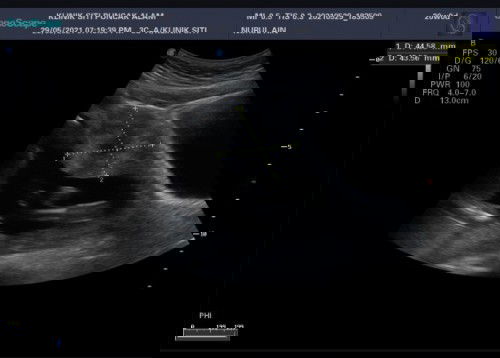

Ni last scan 20w. doc suspect fibroid, tp belum confirm. baru dpt surat nak pegi refer hospital. jumpa pakar. risau.. sbb kalo betul fibroid, position dia dekat dgn laluan baby nk keluar kalo brsalin normal. anak 2org sblm ni dua2 bersalin normal, jadi sy mmg tak bersedia langsung kalo doc suggest czer in case betul fibroid & makin besar. akan ada mslh utk brsalin nnt.. ada yg boleh share pengalaman, nak tenangkan hati niπ«#ingintahu #bantusharing